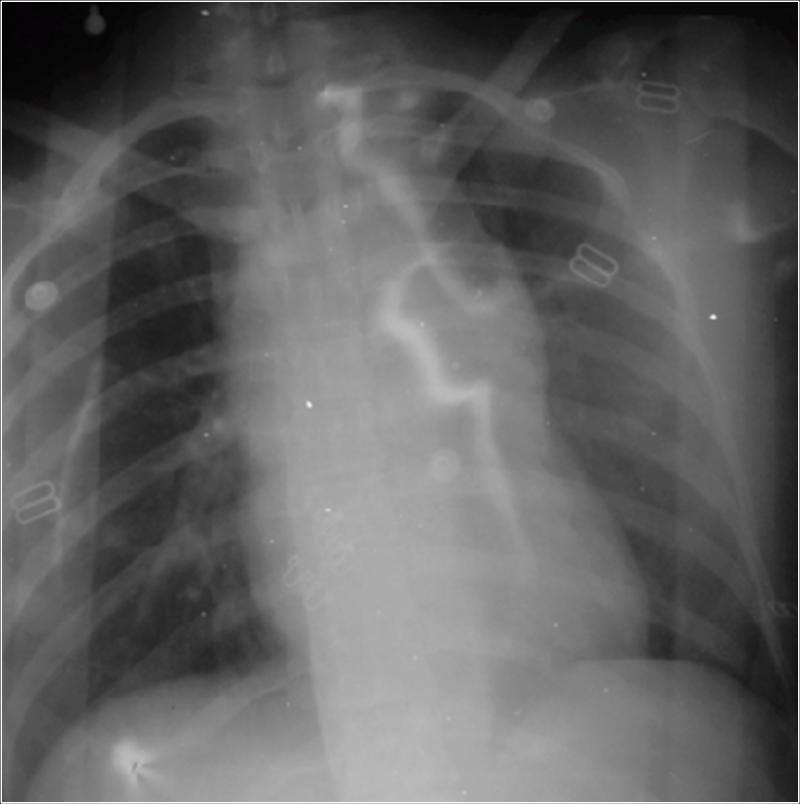

Because the bleeding was contained and she has just a little hemodynamic instability, the choice was endovascular treatment of traumatic thoracic aortic rupture.

A CT Scan was ordered preoperatory: